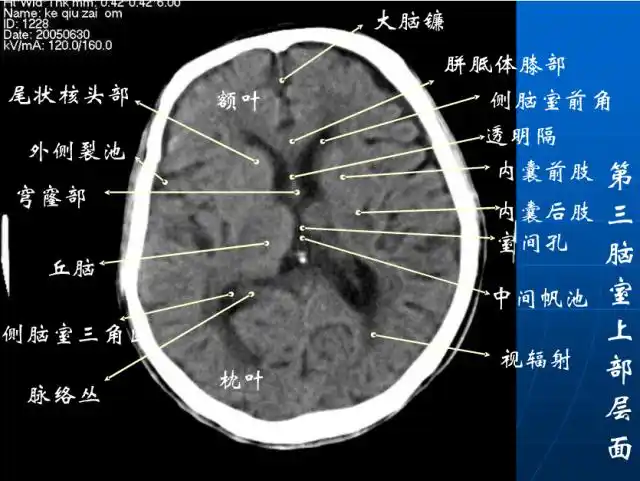

超实用急诊头颅ct3b阅片法

头颅ct 解剖图谱,人手一份

头颅ct解剖与常见出血梗死判读

珍藏| 颅脑ct断面解剖彩色图谱